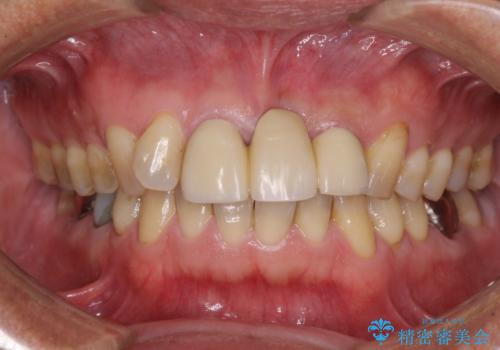

不自然な前歯のブリッジをオールセラミックできれいに

- 保険診療の前歯のブリッジが、形態も色も不自然で気になるとのことで来院された患者様です。

神経の抜かれている土台の歯は根管治療を行った上で、オールセラミックブリッジにより補綴することとしました。

術前の状態より、欠損部位には歯肉移植術が必要と思われましたが、仮歯で調整したところ自然な歯列となったため、外科処置は行わずに自然な口元に仕上がりました。